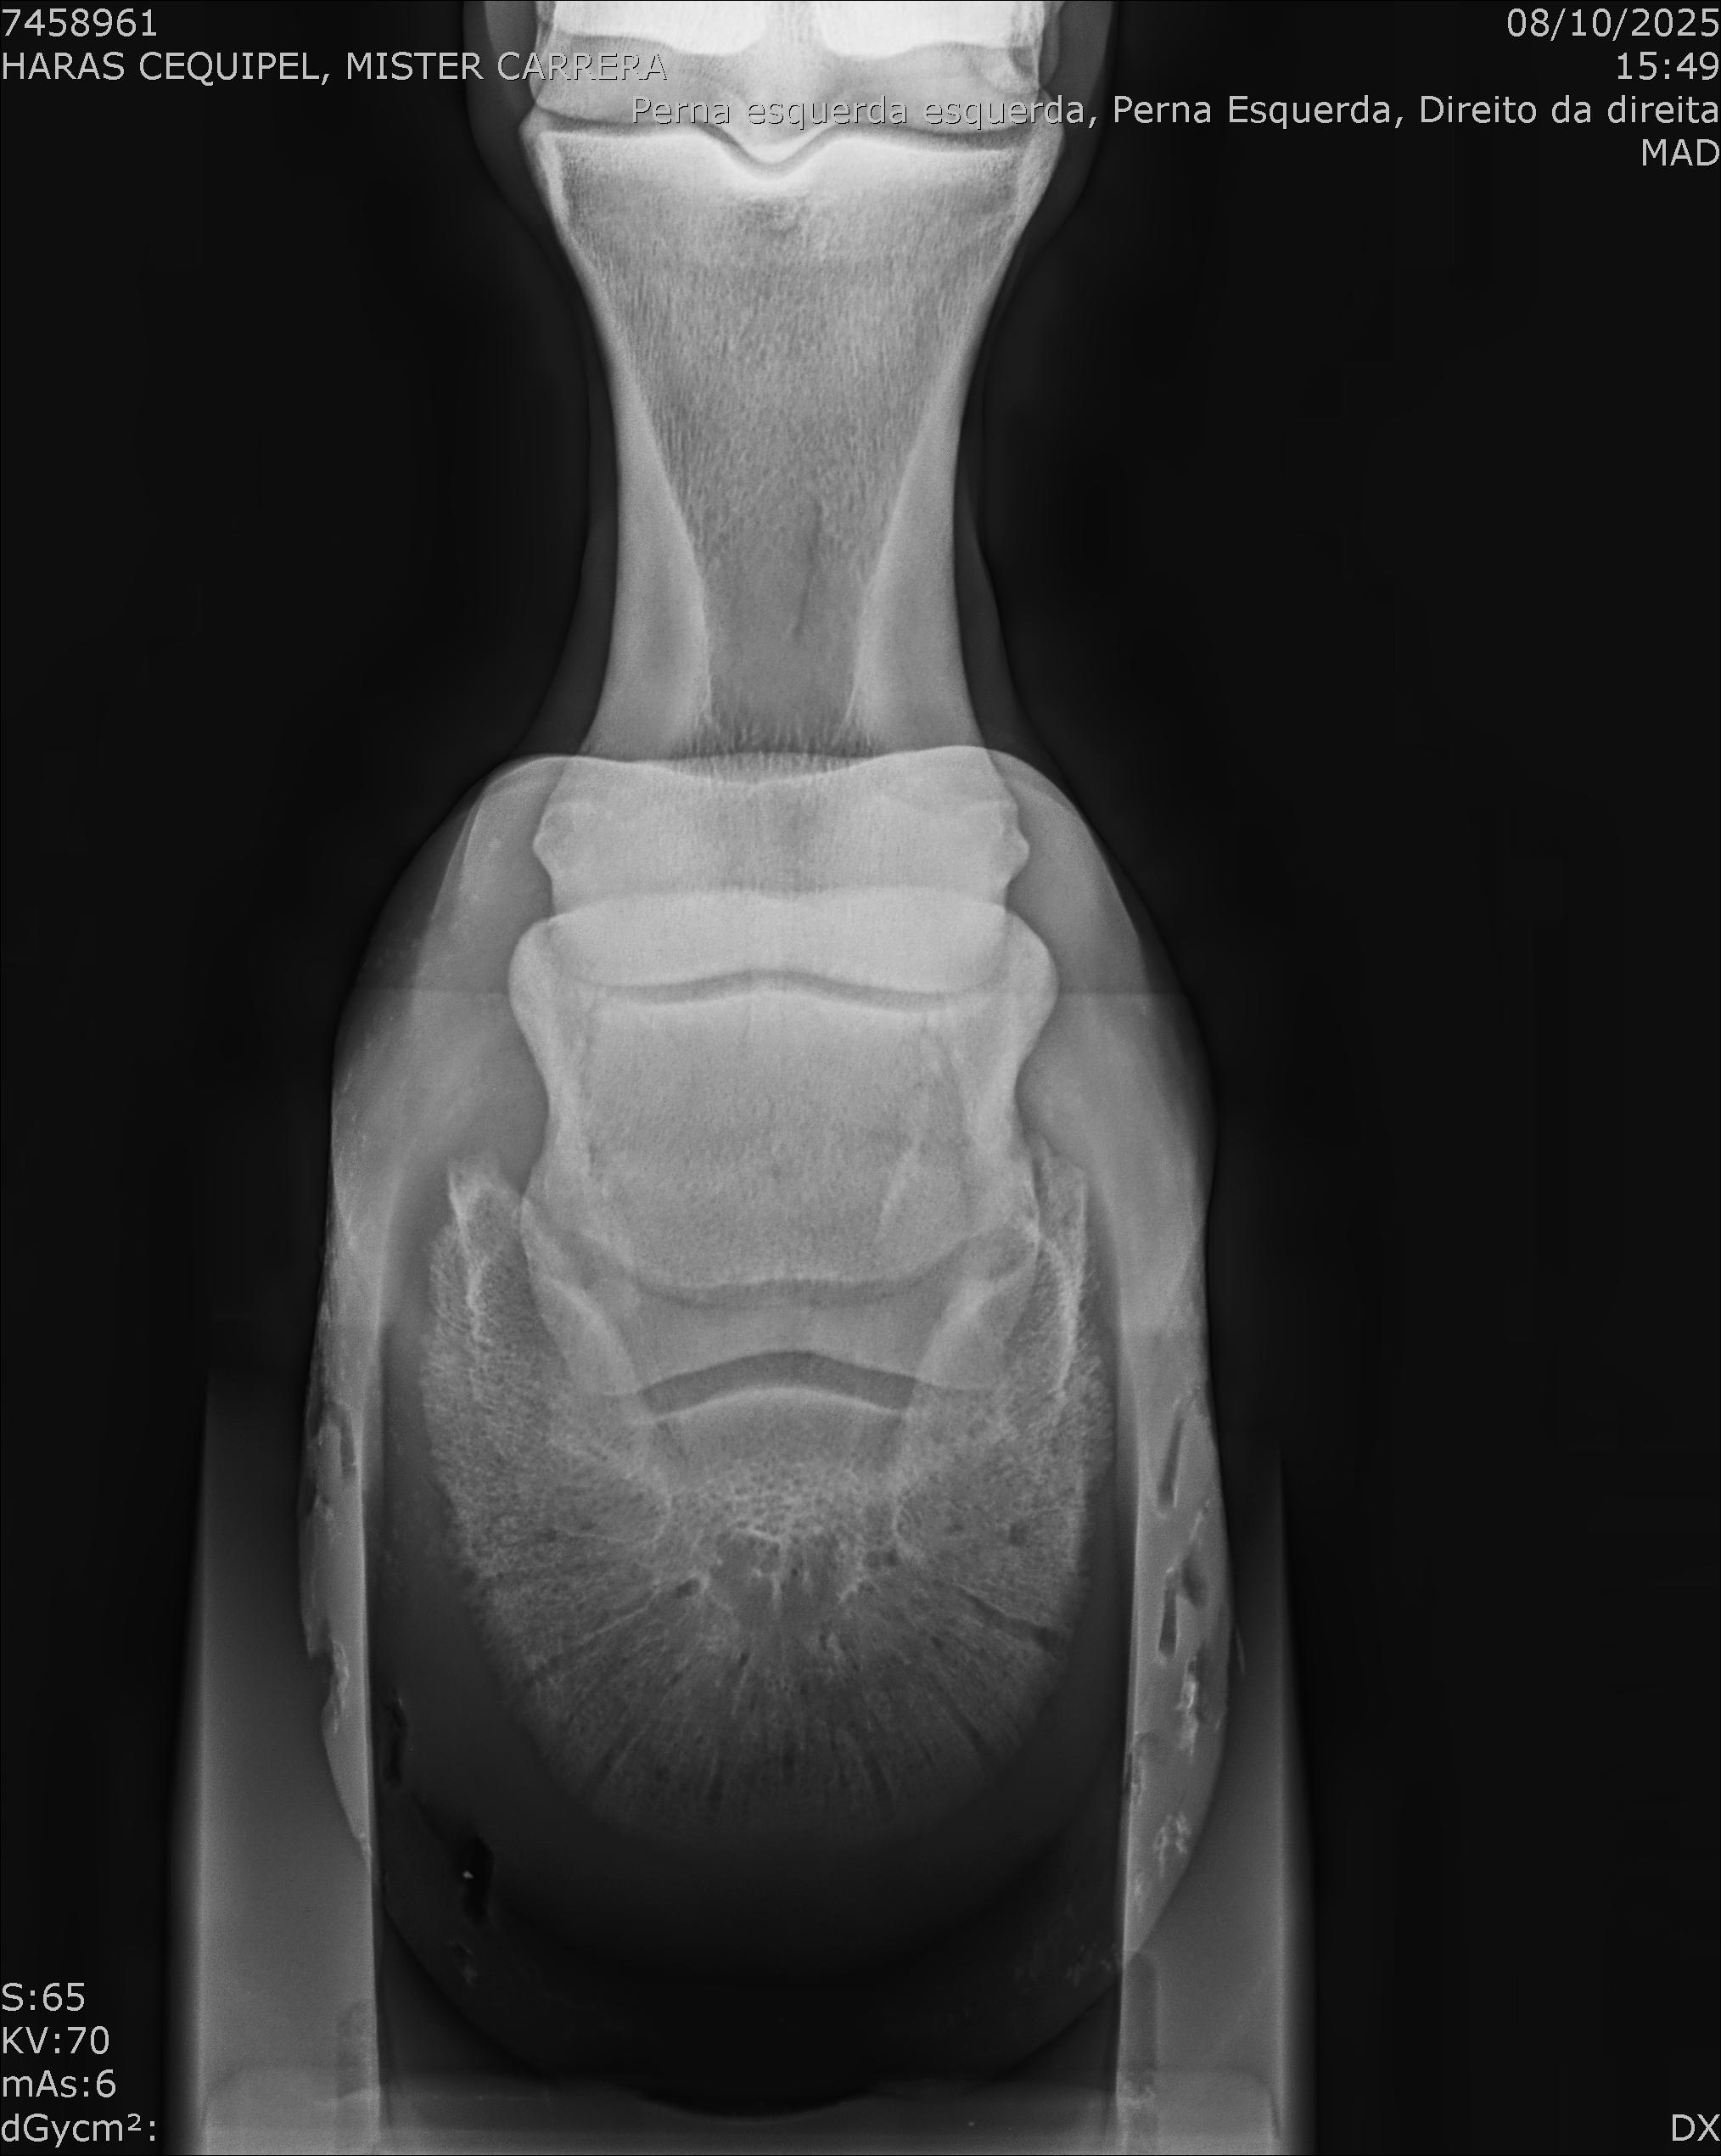

:: RAIOS-X DO LOTE